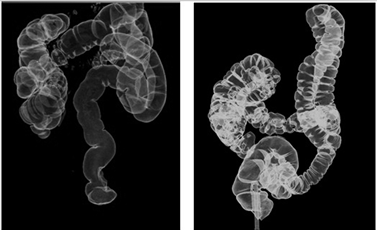

西安天颐堂中医院权威肿瘤专家王三虎接诊了李大爷,在了解李大爷相关病情后,建议李大爷做一下全方位的检查,好确诊疾病。最后发现,李大爷患有轻微的结肠瘤,因此导致便血现象。王教授决定立即采用中医“p53抗癌基因激活疗法”进行治疗。